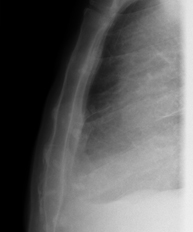

- RX Tòrax

Tècnica que usa els raigs X a través de la qual s'obtenen imatges de la caixa toràcica (cor, pulmó, arcs costal, clavícules, etc.) per al seu estudi. - RX Ester

Tècnica que usa els raigs X a través de la qual s'obtenen imatges dels sins paranasals per al seu estudi. Indicacions: cefalea, tos crònica. - RX Tòrax

Una radiografia de tòrax és una tècnica mitjançant la qual, amb l'ús d'una petita dosi de radiació, s'obté una imatge bidimensional de la caixa toràcica i el seu contingut (pulmons, cor, mediastí, etc. ). És una de les proves mèdiques realitzades més comuna. - RX Abdomen